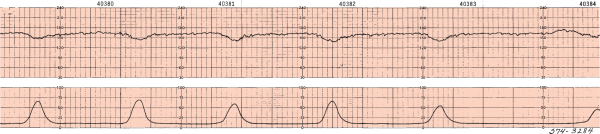

aceler.png

brad.png

des prec.png

des tard.png

des var.png

fcf_norm.png

taq.png

variabilidad.jpg

variabilidad_reducida.jpg